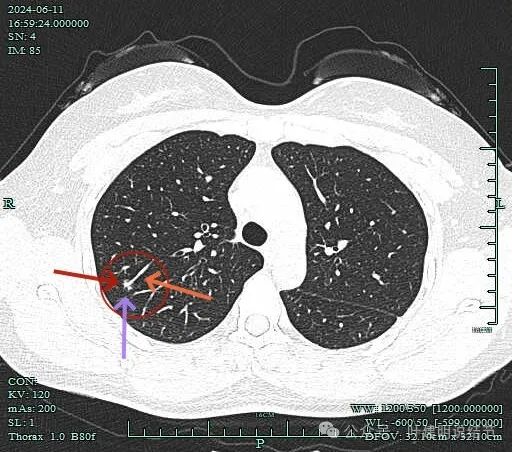

先看2024年6月的影像:

血管有异常增粗的表现,病灶表面有毛刺,灶内实性成分明显,此层磨玻璃成分占比少。